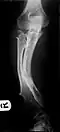

The diagnosis of HMO is based upon establishing an accurate correlation between the above-mentioned clinical features and the characteristic radiographic features. Family history can provide an important clue to the diagnosis. This is supplemented by testing for the two genes in which pathogenic variants are known to cause HMO namely EXT1 and EXT2. A combination of sequence analysis and deletion analysis of the entire coding regions of both EXT1 and EXT2 detects pathogenic variants in 70–95% of affected individuals.[3][7] The hallmark of radiographic diagnosis is the presence of osteochondromas at the metaphyseal ends of long bones in which the cortex and medulla of the osteochondroma represent a continuous extension of the host bone. This is readily demonstrable in radiographs of the knees.[3][1]